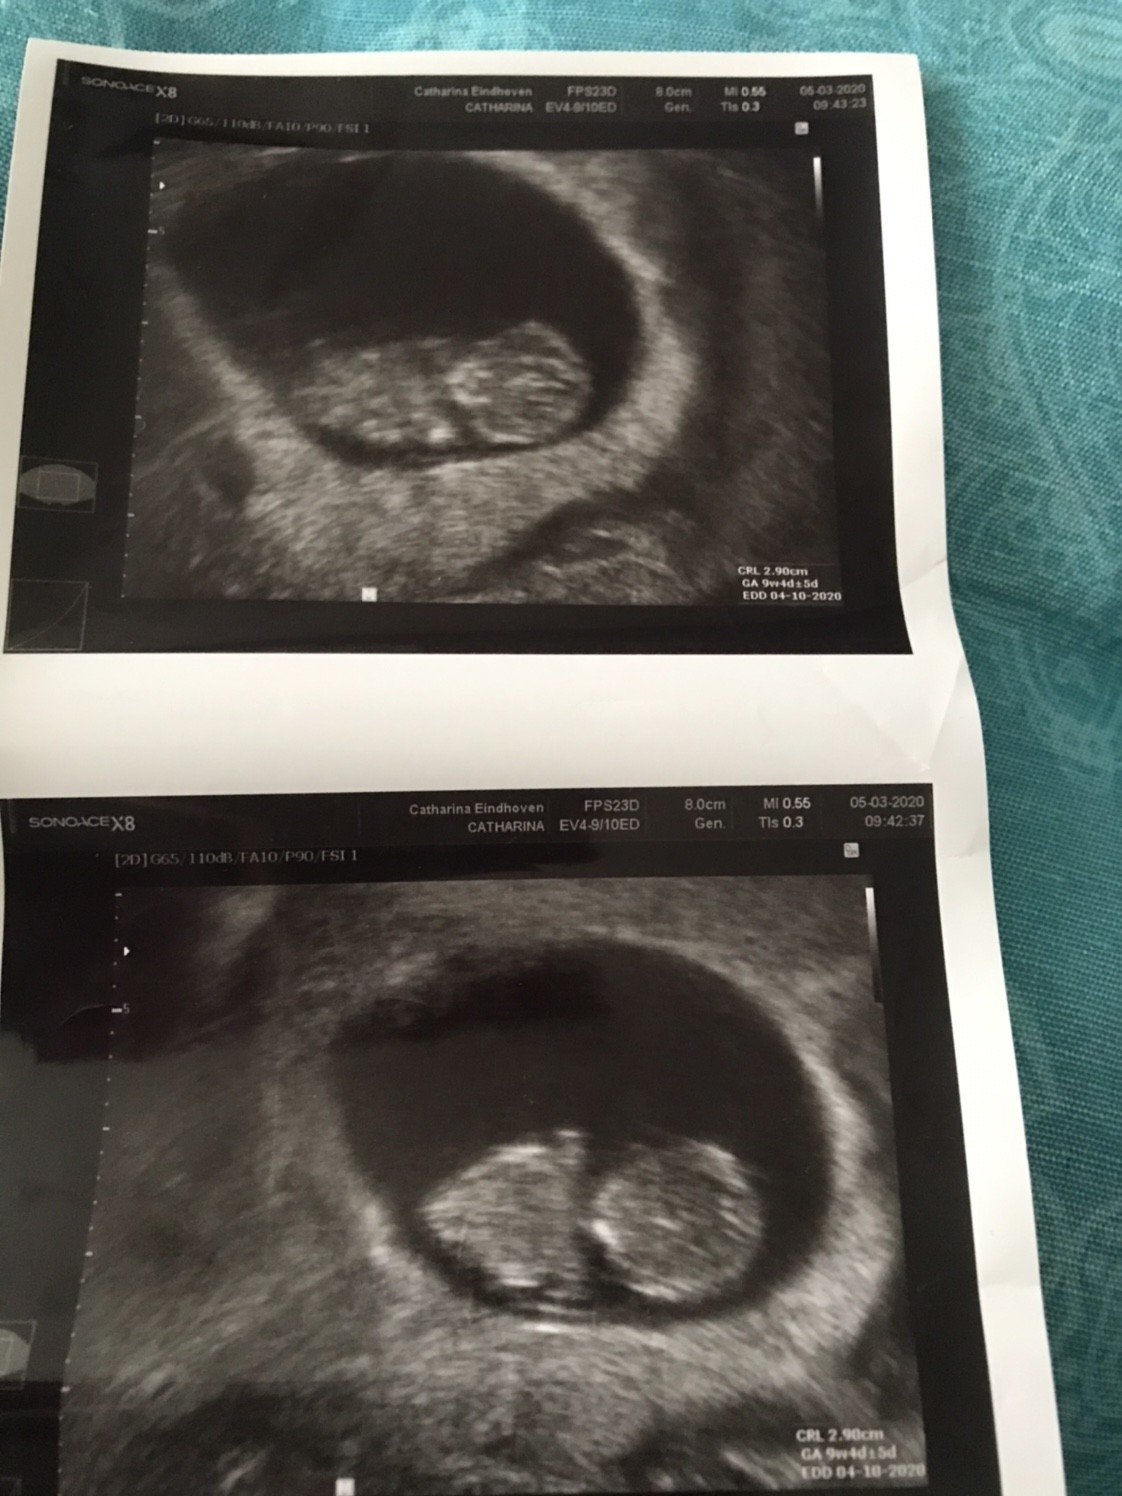

Dziewczyny w końcu dotarłam do domu. A wiec na dzień dzisiejszy wszystko jest dobrze. Maluszek ma nóżki i raczki, kręgosłup i szczękę - i oczywiście serduszko [emoji3059]

Po naciśnięciu ręka brzucha maluszek się ruszał a tak to spał.

Mamy 2,90cm i jest to 9+4 (wg om 9+5)

Termin porodu wpisany w zaświadczenie o ciąży 4.10.2020

A to nasz model/ka

Zobacz załącznik 1088033

Zobacz załącznik 1088034

Następna wizyta już idę do ginekologa zwykłego ale nadal w szpitalu

Także 17.03 usg i spotkanie z nowym lekarzem

20.03 konsultacje przed badaniami prenatalnymi.